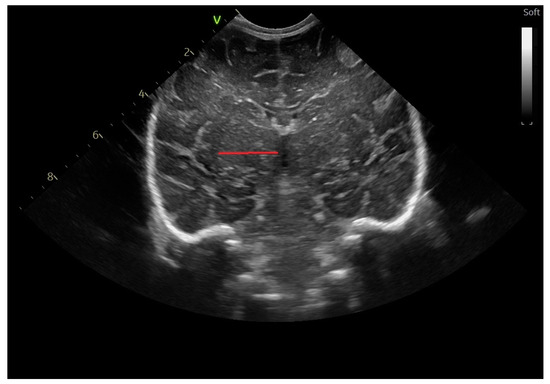

2.2. Head Ultrasound Measurements at TEA